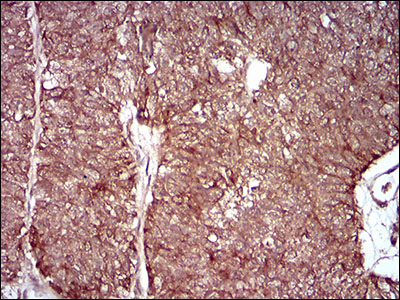

Immunohistochemical analysis of paraffin-embedded human ovarian cancer tissue using anti-MMEL1 antibody. Counter stained with hematoxylin.

Immunohistochemical analysis of paraffin-embedded human cervical cancer tissue using anti-MMEL1 antibody. Counter stained with hematoxylin.